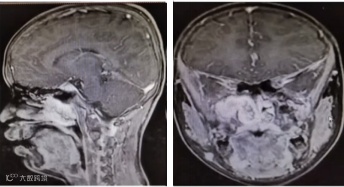

MRI检查:以稍长T1混杂T2信号为主,沿翼腭窝、上颌窦后壁向周围蔓延生长,病灶边界欠清,向上达右侧海绵窦,向后达鼻咽腔右侧壁,向外达右侧颞窝,向下达软腭平面,病灶累及右侧翼外肌,病灶无明显异常扩散受限信号影;左右径4.7cm,前后径3.8cm,上下径3.4cm,三维容器增强扫描病灶早期呈较明显不均匀斑点强化,延迟病灶内强化范围加大,持续强化。(见下图)